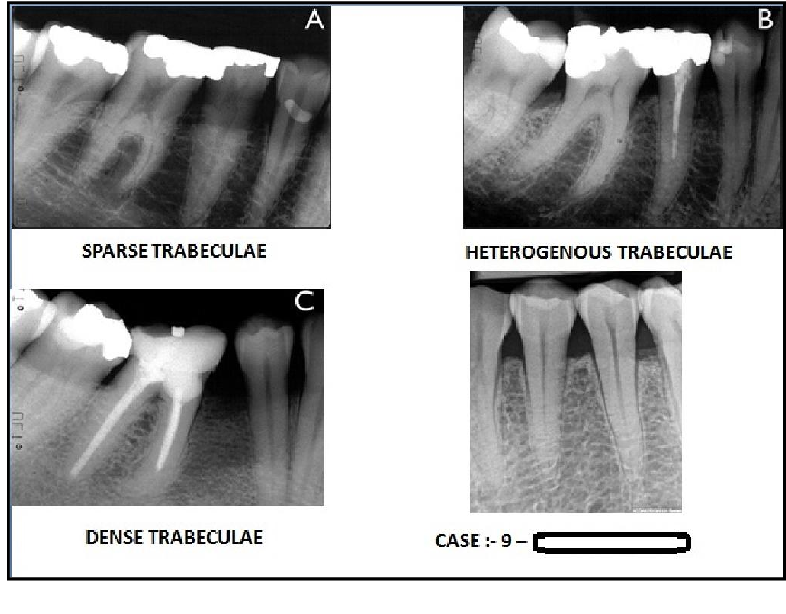

Trabelculae

Interconnected spongy bone (bony lines) that appear like fuzzy bright lines and dark spaces